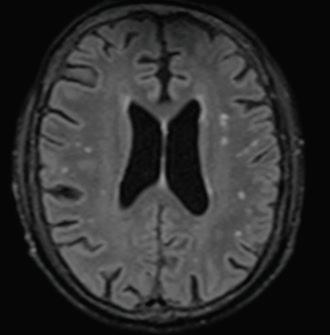

Бяха проведени следните диагностични изследвания - компютърна томография (КТ) на глава, лумбална пункция и магнитно-резонансна томография (МРТ) на главен мозък. При разчитането на КТ на глава не бяха установени данни за огнищни или дифузни промени, нетипични за възрастта (Фиг. 1).

Фиг. 1

КТ на главен мозък за възрастта Фиг. 2 МРТ на главен мозък (Т2-режим) с данни за съдова левкоенцефалопатия